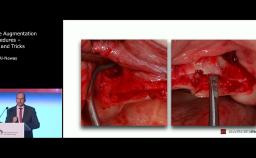

Surgical Planning and Procedures

ITI World Symposium 2024 lecture by Mauricio Araujo - part of the "GBR/Bone Augmentation" session.